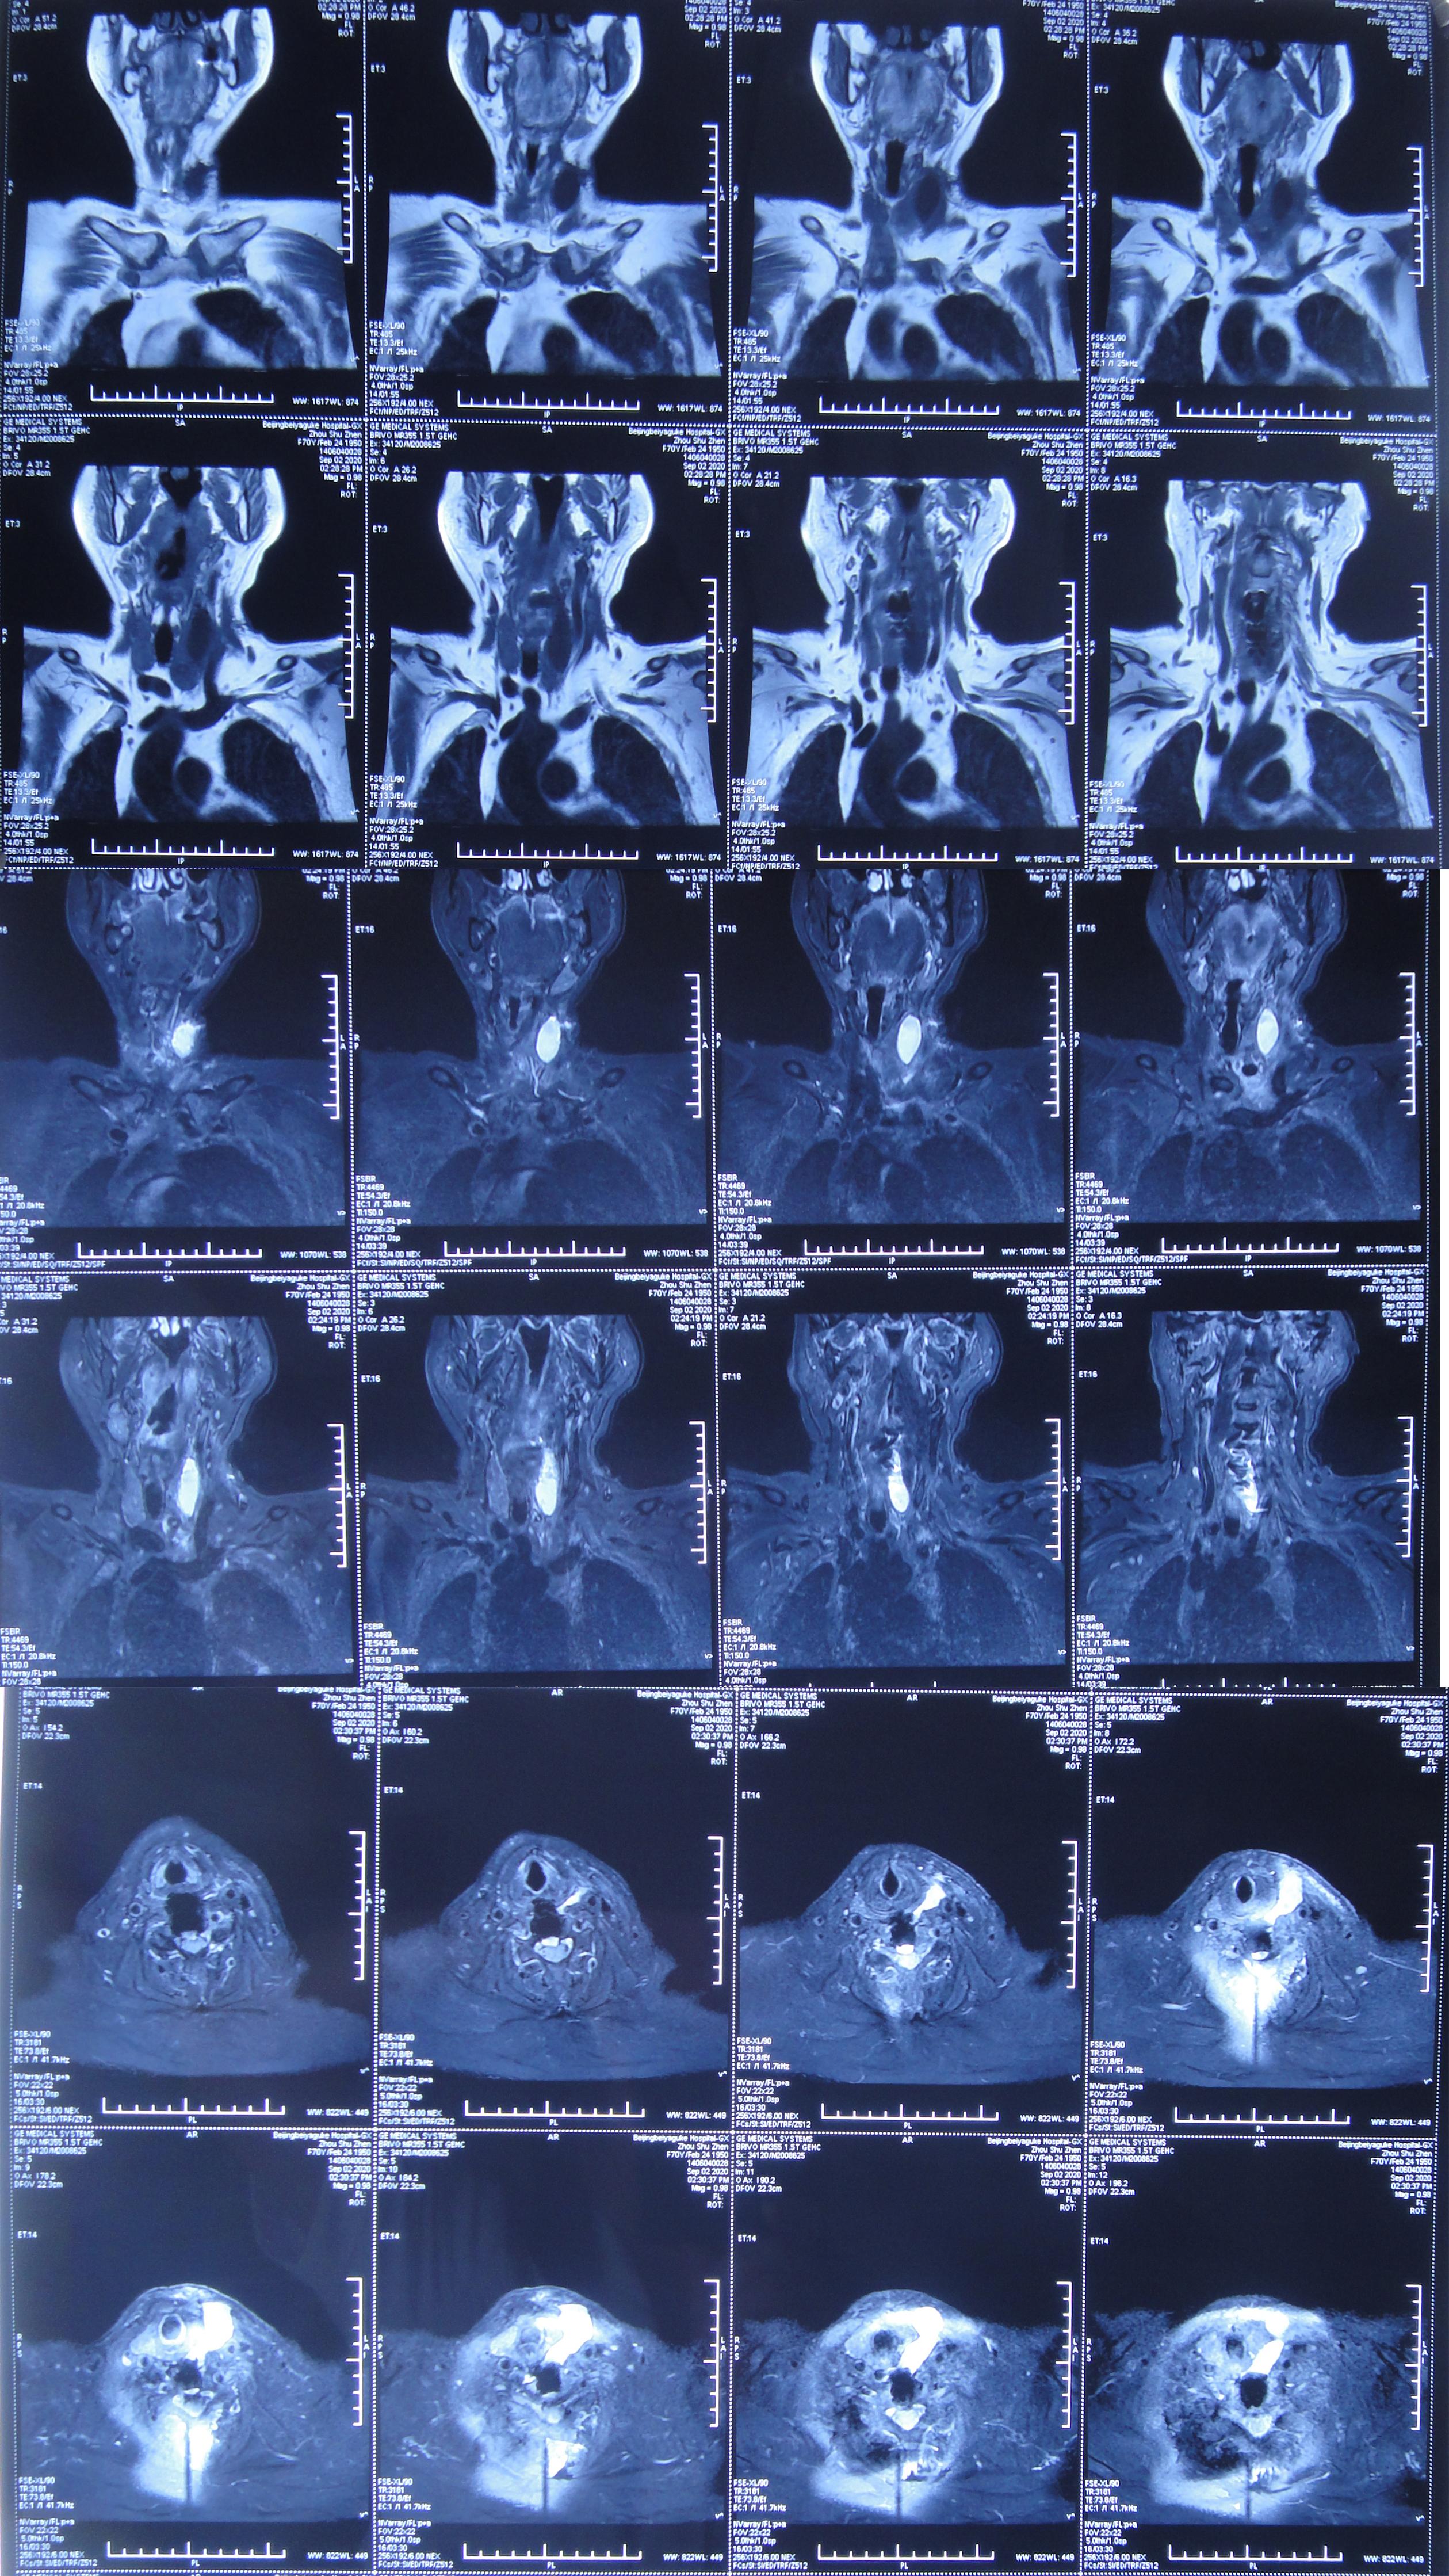

患者因间断性头晕、行走不稳,伴双上肢放射痛,麻木,于2020年4月11日入住北京某三级医院的中医骨伤科,当日查颈椎CT示椎管狭窄性颈椎病(图-1)。

图-1: 2020年4月11日颈椎CT

入院后第二天2020年4月12日查颈椎MR示颈椎病(脊髓型)( 图-2 )。

图-2: 2020年4月12日颈椎MR

2020年8月1日(即第一次颈椎病术后第101天)患者复查颈椎MR示颈椎病,椎管狭窄,颈髓受压( 图-5 )。

图-5: 2020年8月1日颈椎MR